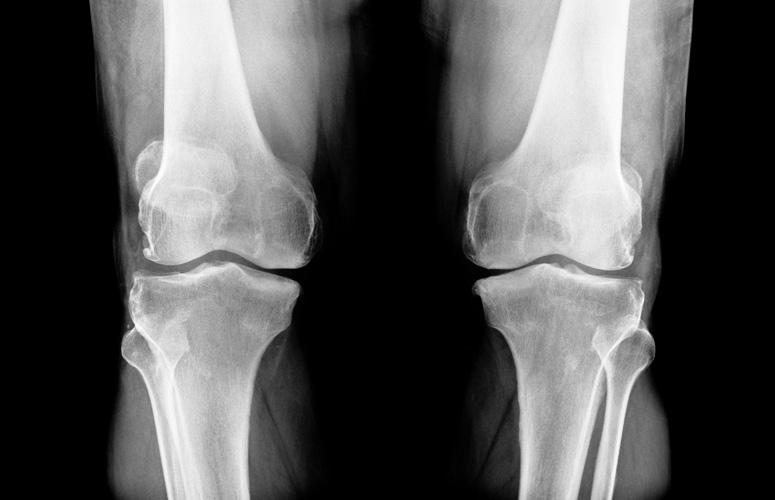

Osteoporosia: zer jan behar dugu prebenitzeko?

Nekagarria da orno bat, beso bat edo aldaka hausteko beldurrez bizitzea. Horixe gertatzen zaie, hain zuzen ere, osteoporosia dutenei, hau da, “hezur porotsuak” dituztenei. Gaixotasunaren ezaugarria da murriztu egiten dela hezur masa, eta 50 urtetik gorako emakumeen % 50i eta gizonen % 8ri eragiten die.

Osteoporosiarekin batera doan hezurren hauskortasunak murriztu egiten du gaixotasuna duten pertsonen bizitza, eta erikortasun eta heriotza tasa handiekin lotzen da. Gainera, maiz gaixotasun desgaitzaile bihurtzen da.